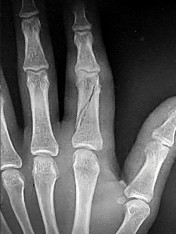

- الكسور: تُعد كسور عظام اليد والمعصم من الأسباب الشائعة للألم والخلل الوظيفي. تتضمن كسور السلاميات، العظام المشطية، عظام الرسغ (مثل كسر العظم الزورقي)، وكسور الكعبرة البعيدة (Distal Radius Fractures). قد تحدث هذه الكسور نتيجة السقوط على يد ممدودة، الإصابات الرياضية، أو حوادث السيارات.

- الأشعة السينية (X-rays): هي الخطوة الأولى في تقييم الكسور، الخلوع، وتغيرات التهاب المفاصل. تساعد في تحديد مدى تدهور العظام والمسافات المفصلية. على سبيل المثال، تُظهر صور الأشعة السينية كسور السلاميات

أو كسور قاعدة العظم المشطي الخامس

، بالإضافة إلى علامات مثل "الدمعة الشعاعية" (Radiographic Teardrop) في الرسغ التي تمثل الزاوية الزندية الراحية الحرجة للكعبرة البعيدة